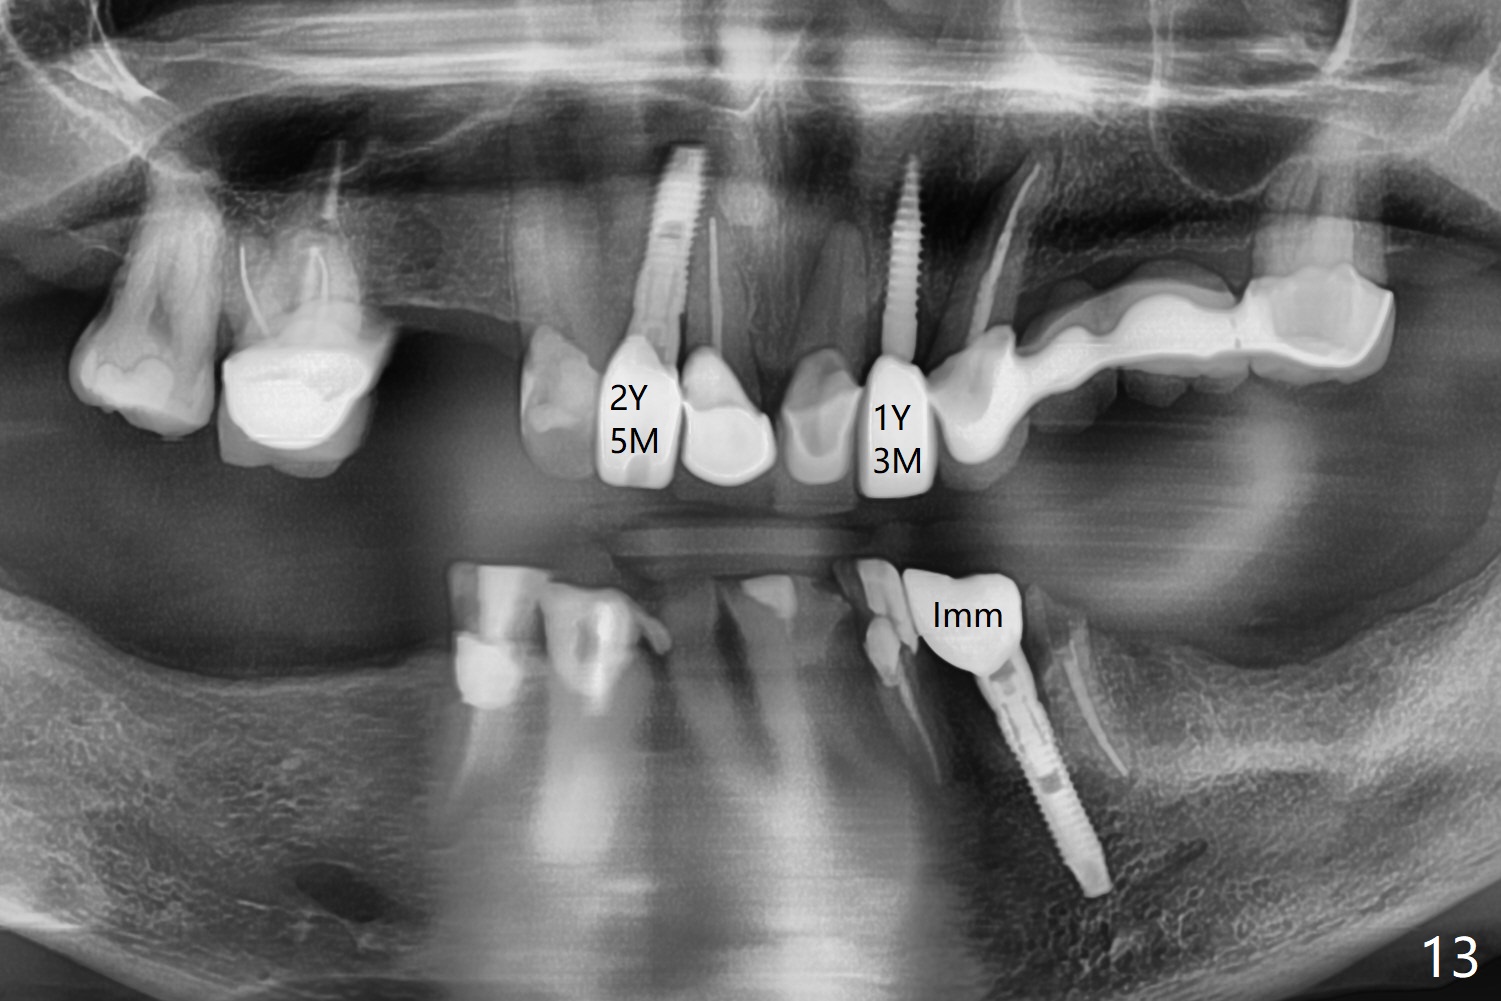

After removal of the split residual roots at #22 (Fig.1), the buccal wall is found to be defective, while the coronal portion of the lingual one (Fig.2 L) is confirmed to be more buccal than the apical portion. A vertical slot is made in the coronal portion of the lingual plate (Fig.3 *) in order to establish osteotomy lingual (Fig.4 O). The depth of the osteotomy in the apical native bone is 4.8 mm (Fig.5 CT coronal section). After the final drill (3 mm) is removed, a 3.8x16 mm implant is placed lingually for secure 2-pointed fixation (Fig.6,7, coronally: mesiolinguodistal; apically: in the native bone (Fig.9)). The essence of the lingual placement is the presence of a large buccal gap for Osteogen plug (Fig.8 yellow) and allograft (Fig.8 red, 9,10 (*)) for potential regeneration of the buccal plate. With bone graft and the overlying provisional (Fig.11 P), the buccal plate seems to have been established (*) 1 week postop. There is no obvious implant thread exposure 8 months postop (Fig.12). But the buccal plate is atrophic when the crown is cemented (~10 months postop, Fig.13).